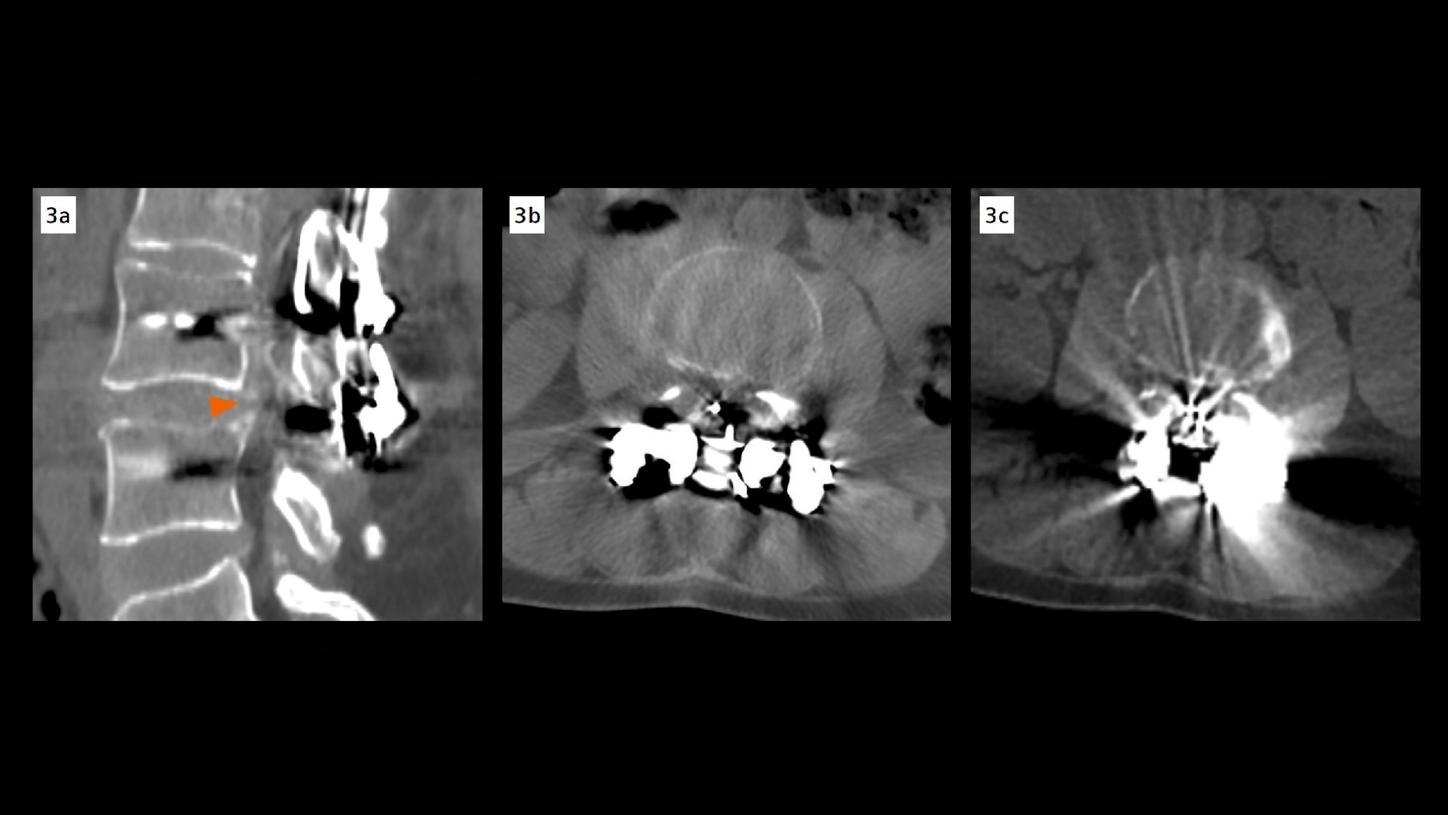

Dual energy CT images with iMAR revealed a fracture of the L4 transpedicular screws and posterior pseudoarthrosis at the L3–L4 level, which were not clearly visible in the previous multislice CT due to extensive metallic artifacts (Fig. 1). Additional findings included diffuse bulging of the L3–L4 intervertebral disc, facet joint nonunion, and posterior fixation hardware contributing to moderate spinal canal stenosis (type C according to Schizas [1] – L3–L4 canal compromise) (Fig. 3). A subarticular and left foraminal protrusion of the L5–S1 disc was also observed, partially occupying the left lateral recess and compressing the exiting nerve root (type D – L5–S1 foraminal impingement) (Fig. 2). The patient is currently being prepared for surgery to address screw failure and pseudoarthrosis. Surgical planning also includes decompression of the L5–S1 nerve root.

Fig. 3: Axial and sagittal CT images of the lumbar spine at the L3–L4 level. (A, B) Sagittal and axial image reconstructed using iterative metal artifact reduction (iMAR) combined with high-energy monoenergetic imaging (140 keV), show markedly improved visualization of the prosthetic components and surrounding anatomy, revealing moderate spinal canal stenosis. (C) Axial image acquired on a previous standard multislice CT scanner, with prominent metal artifacts that obscure the spinal canal and adjacent structures.